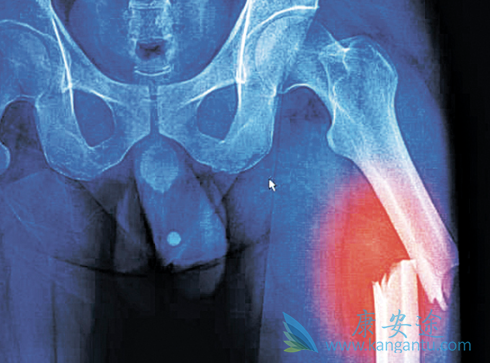

会导致骨质疏松,这多是长期服用激素的后果,那么患者在服药期间应注意补充钙剂,尤其是骨髓瘤患者,本就伴有溶骨性破坏,要格外注意。④大剂量激素与化疗药相似,都会导致患者机体免疫力降低,导致感染的几率增加,尤其是年龄较大,体质虚弱的患者,要警惕出现感染或病情反复加重现象,可以同时加服中药减缓不良反应。血液科医生介绍,在多数血液病治疗过程中,激素常常是必备药物,而患者也总是非常排斥激素的使用,其实,规范使用激素对病情控制效果显着,尤其是配合中医辨证治疗,可增加对病情的有效控制!